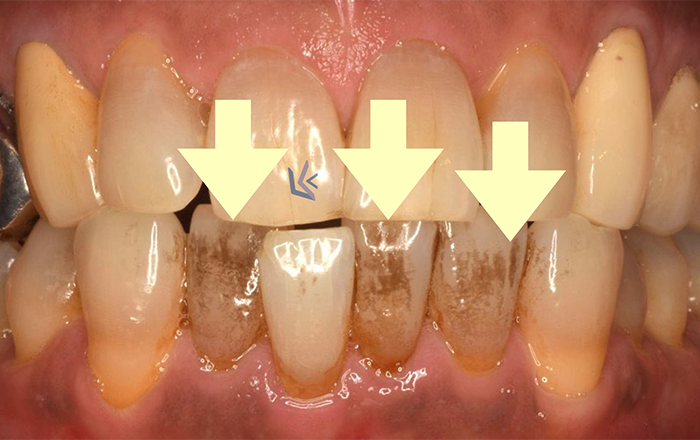

歯の着色として、大きく分けて2種類が考えられます。

1)コーヒーなどの着色物

ポリフェノールを含んでいる飲み物・食べ物を口にすると、歯が着色します。

コーヒー・お茶・カレー・ワインなどです。

日常的に食べたり飲んでいる人は、着色しやすいです。

2)タバコに含まれるヤニ

タバコに含まれているヤニは、歯につくことで着色します。

また、歯ぐきの黒ずみも引き起こします。

歯に着色した場合は、歯科医院のお掃除で綺麗にすることができます。